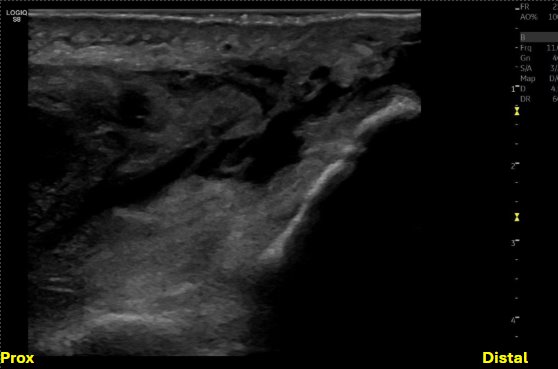

Short axis view at the level of the distal humerus, evaluating the triceps tendon/muscle, posterior fat pad, and olecranon fossa

Unlabeled short axis view at the level of the distal humerus proximal to the olecranon fossa, evaluating the triceps tendon/muscle with evidence of bony avulsions.

Labeled short axis view of the distal triceps tendon stump showing loss of normal fibrillar structure of the triceps tendon, with discrete bony avulsions within the retracted triceps tendon. There is anechoic and hypoechoic fluid signal, compatible with hematoma or seroma formation.